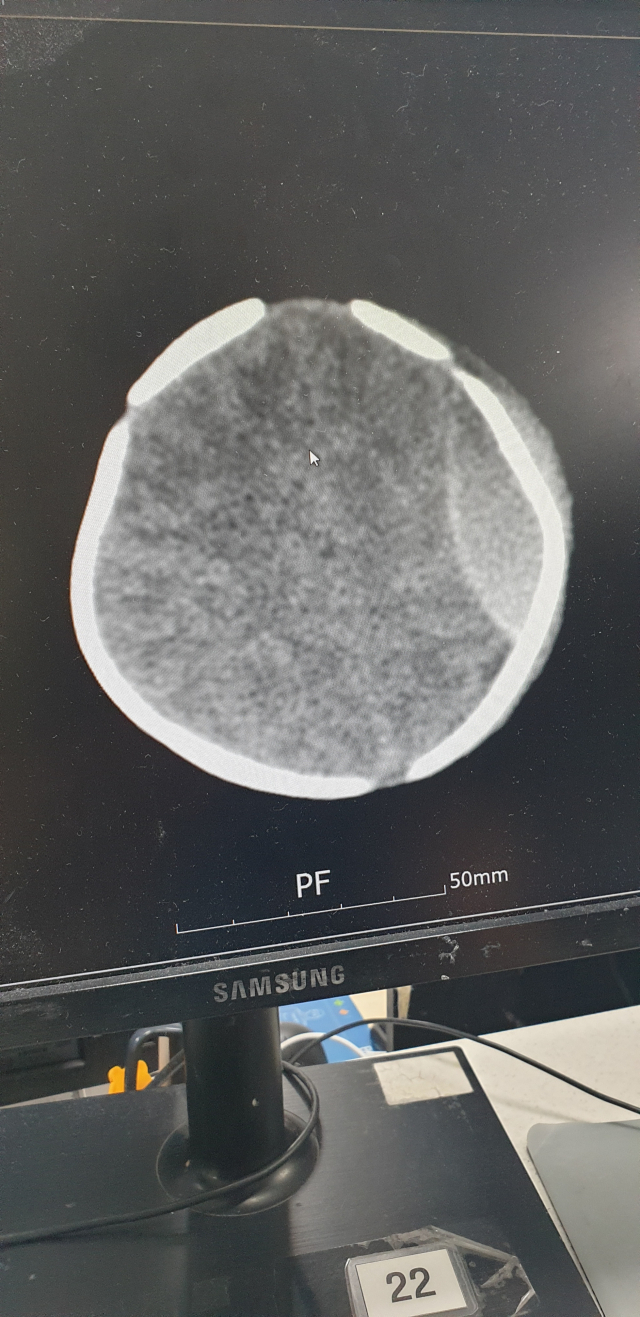

한편 같은 산후조리원에서 지난달 28일 생후 13일 신생아가 처치대에서 떨어져 머리를 다쳐 경찰이 간호조무사 D 씨를 업무상 과실치상 혐의로 입건해 수사하고 있다. 사진은 낙상 피해 아기 머리 CT 사진. 낙상 피해 부모 측 제공 한편 같은 산후조리원에서 지난달 28일 생후 13일 신생아가 처치대에서 떨어져 머리를 다쳐 경찰이 간호조무사 D 씨를 업무상 과실치상 혐의로 입건해 수사하고 있다. 사진은 낙상 피해 아기 머리 CT 사진. 낙상 피해 부모 측 제공

신생아 낙상 피해 부모 측은 사고 23시간 뒤인 지난달 29일 오후 12시 이후 사고 소식을 접했다. 아기는 대학병원으로 옮겨졌는데, 뇌출혈 등이 확인돼 지난달 30일 수술을 받고 회복 중이다. 낙상 피해 부모 측은 “아이가 다치고 나서 ‘수유콜’을 받아 수유를 했다”며 “사고 사실을 더 일찍 알릴 기회가 분명 여러 번 있었는데 그걸 놓쳤다는 점이 가장 갑갑하다”고 밝혔다.